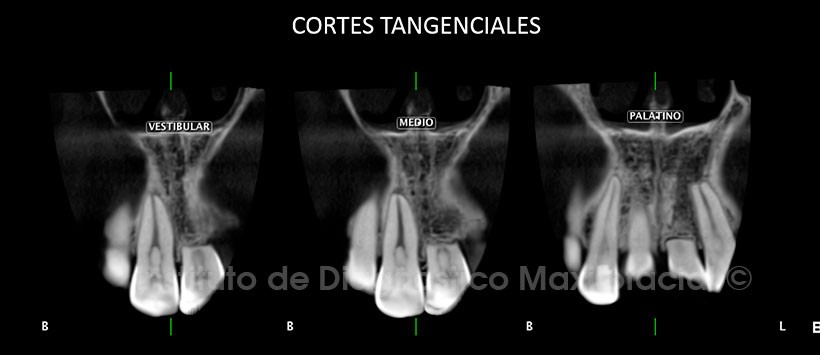

A la evaluación de la tomografía volumétrica (CBCT) en cortes axiales (Figura 2), transaxiales (Figura 3) y tangenciales (Figura 4), se evidencia reabsorción radicular externa severa de los dos tercios radiculares de la pieza 2.1 con pérdida total de soporte óseo, material de restauración en borde incisal y en la superficie palatina, presencia de cálculo en cámara pulpar. A nivel de la pieza 2.2 se aprecia leve reabsorción radicular externa a nivel apical y presencia de cálculo en cámara pulpar.